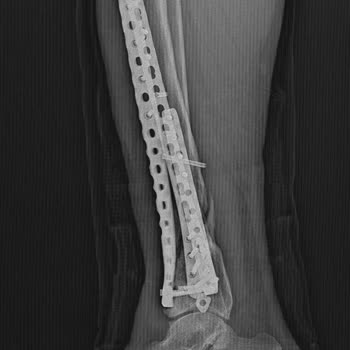

1994 yılında Şişli Etfal Hastanesi’nden görme engelim için aldığım %52 oranlı raporum süresiz verildi. 2004’te yine Şişli Etfal’den bu kez %55 oranlı, süresiz rapor aldım. Yıllarca tüm resmi işlemlerimi bu raporlara dayanarak yaptım, göz hastalığım nedeniyle askerlikten muaf tutulduğum için engel du...